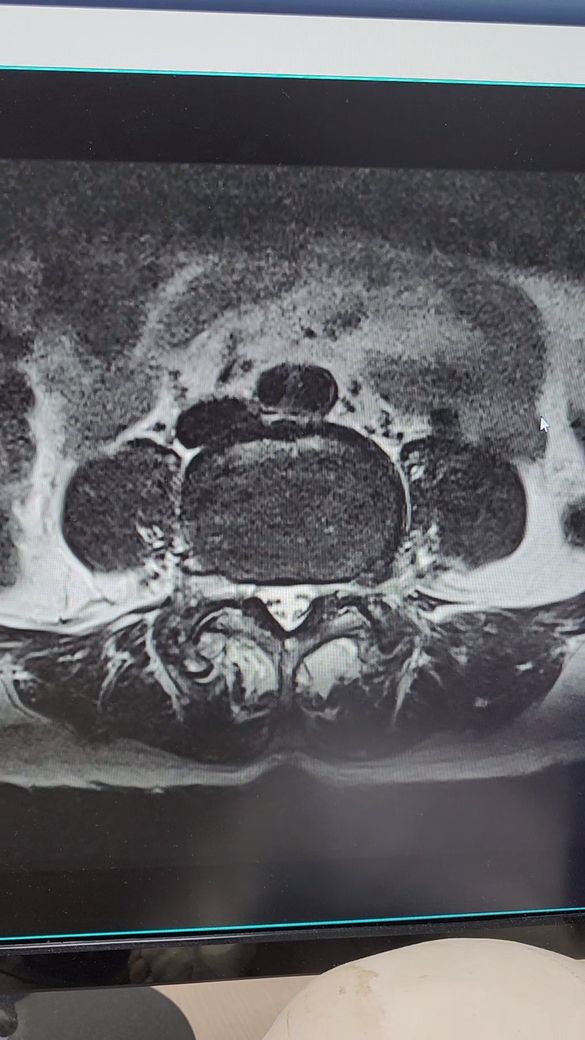

허리디스크 추간판탈출증.전방전위증

4월5일 척추,4.5번

추간판탈출증과 전방전위증으로 왼쪽 엉치부분과 사타구니 허벅지 뒷쪽 방사통과 다리저림이 심해요.처음엔 걷지도 못하고 한달반정도 물리치료,도수치료.약물치료하다가 좋아지질않아서